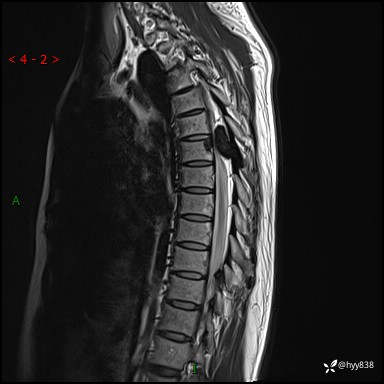

胸椎MRI平扫(sag T1WI+T2WI)